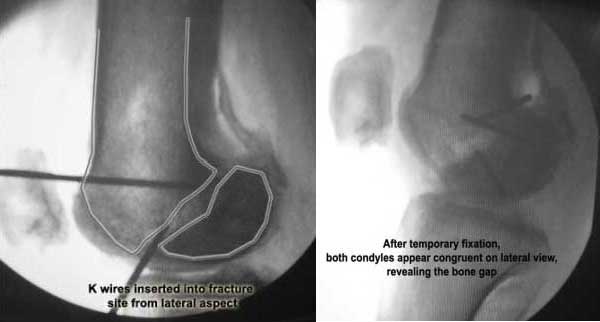

This 20 year old patient sustained a fracture in the lower end of the femur, one and a half years ago, with a compound wound over the fracture area. Notes at that time mention a compound fracture dislocation, with a loss of part of the lateral condyle. This was treated by debridement, and external fixation. After two weeks, the lateral condyle (coronal fracture) was fixed by a screw and k wire in an AP direction.

I opened it up from the lateral aspect.

Freed up the non-union site with minimal disturbance to the posterior and lateral soft tissue attachments on the lateral condyle fragment.

Applied a distractor between femoral shaft and tibia, to create a space on the lateral aspect.

This brought the lateral condylar fragment into a position that seemed to be reasonably well aligned, but showed up a bone gap.

This was fixed temporarily, bone grafted with tricortical struts, and fixed by two cancellous screws. The fragment was not large enough to afford any fixation to a plate or such implant, and the screws held it compressed well to the rest of the distal femur.

Pictures attached.